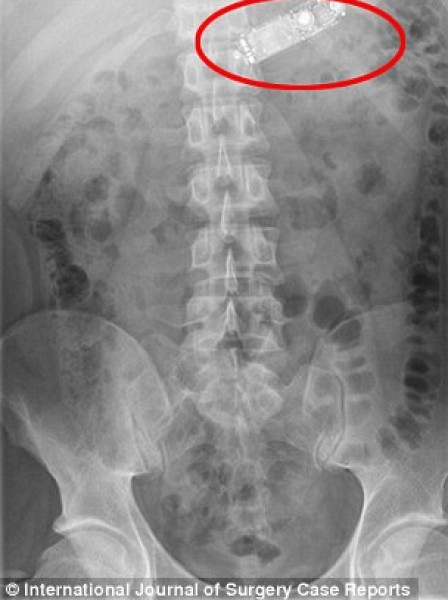

وأظهرت الأشعة السينية جهاز الهاتف وهو موجود في معدة الشاب، وحاول الأطباء اقتلاعه بالمنظار عن طريق المريء، وبعد فشل المحاولة أجبروا على إخضاعه لعملية جراحية عاجلة وشق بطنه لاستخراج الهاتف قبل أن يمزق معدته، وفقاً لصحيفة دايلي ميل البريطانية.